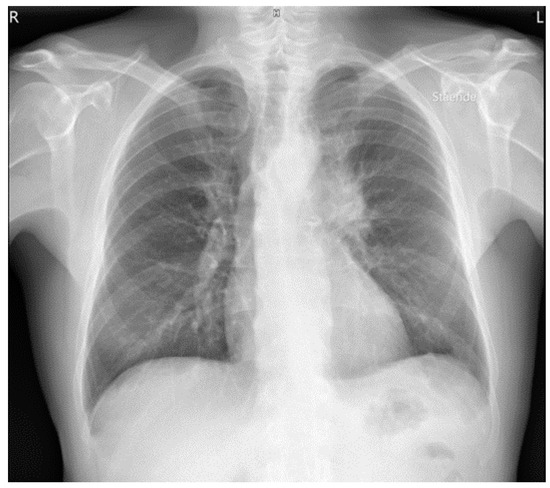

Uncommon Presentation of Granulomatosis with Polyangiitis Mimicking Metastatic Lung Cancer